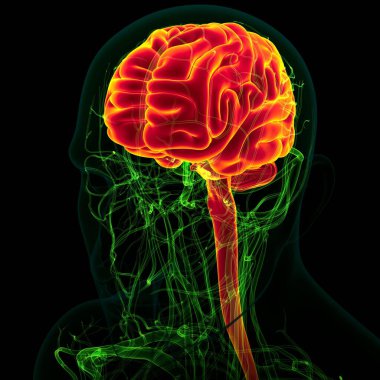

Tıbbi Konsept için sinir sistemi anatomisi olan 3D İnsan Beyni

MaviGrafikselresimlemeŞeffafİnsanSağlıkBaşıİlaçerkekkordonüç boyutlubiyolojikHücregövdeHastalıkİstihbaratİçeridebiyolojiBilimSistemAcıorgzihinomurgaelektronİşaretgörüntü oluşturmaanatomiomurilikbeyinMerkezGerginNörolojimikroskobikBeyin fırtınasıSıhhiyeanatomikSinirbeyincikcerebra3d oluşturmaüzerine siyahsinir hücresiBenzer İçerikler